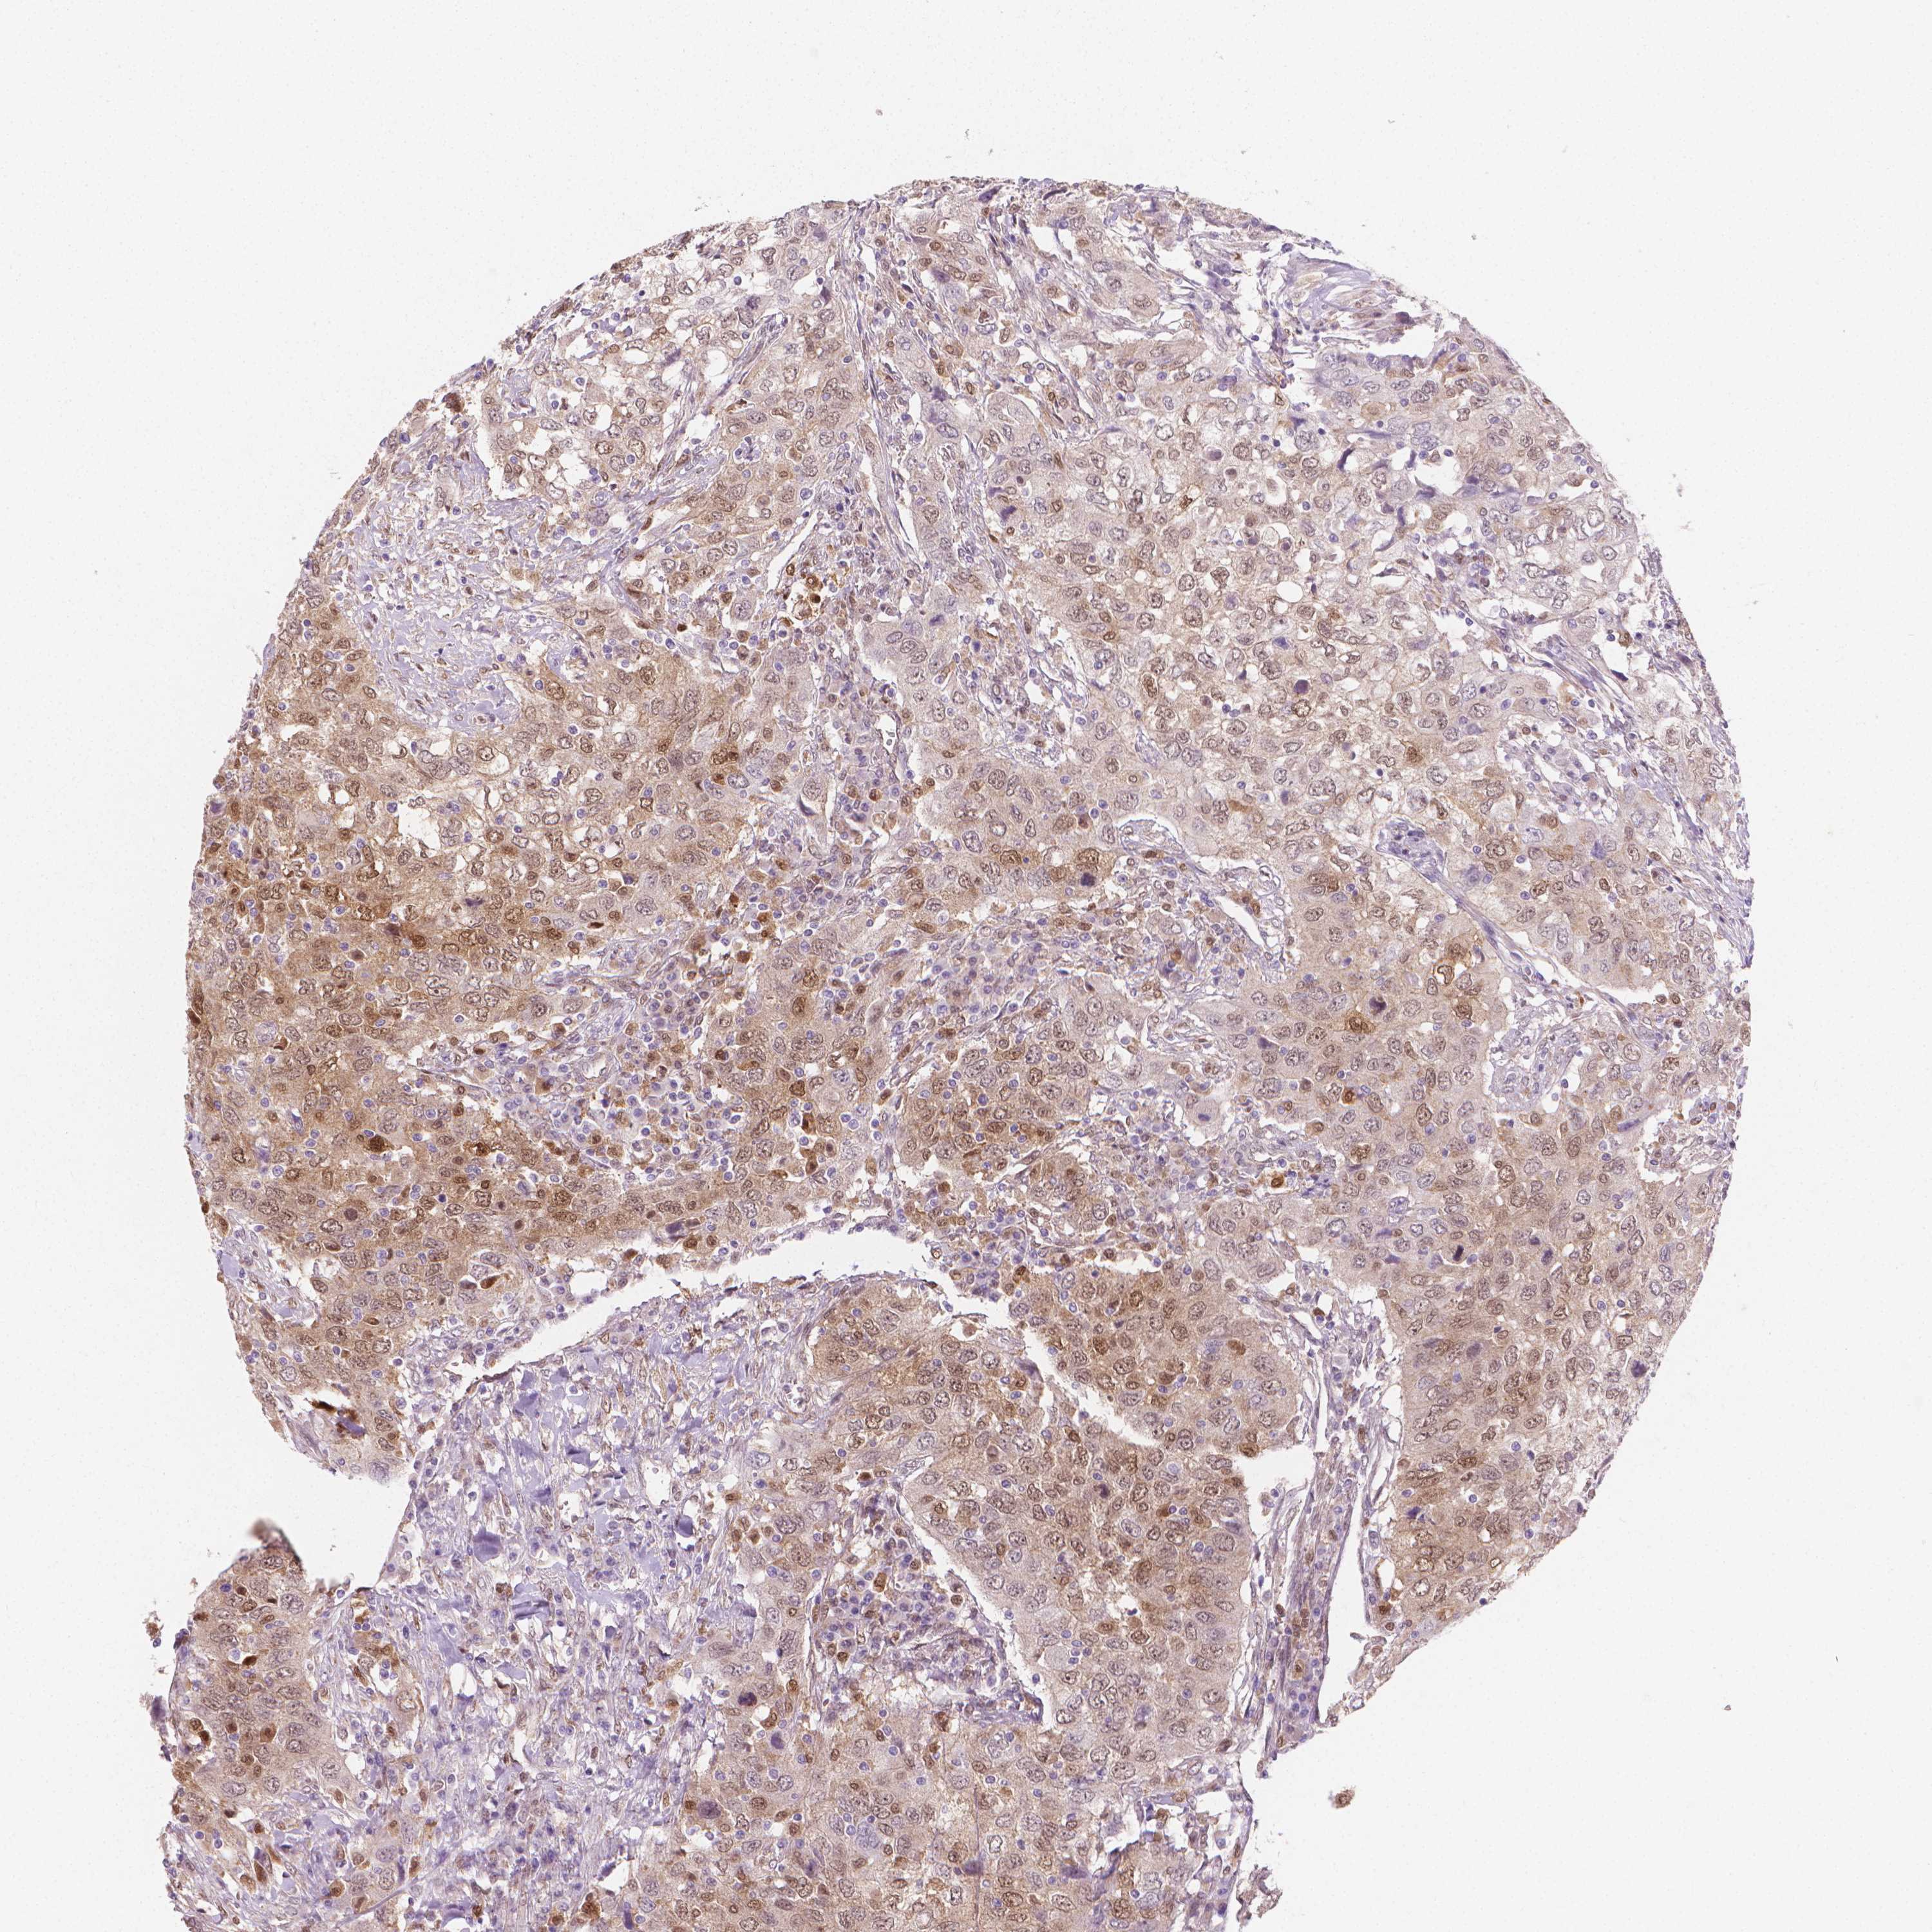

UROTHELIAL CANCER - Protein expressioni

A mouse-over function shows sample information and annotation data. Click on an image to view it in a full screen mode. Samples can be filtered based on level of antibody staining by selecting one or several of the following categories: high, medium, low and not detected. The assay and annotation is described here.

Note that samples used for immunohistochemistry by the Human Protein Atlas do not correspond to samples in the TCGA dataset.

Antibody stainingi

Antibody staining in the annotated cell types in the current human tissue is reported as not detected, low, medium, or high, based on conventional immunohistochemistry profiling in selected tissues. This score is based on the combination of the staining intensity and fraction of stained cells.

Each image is clickable and will lead to virtual microscopy that enables deeper exploration of all samples and also displays staining intensity scores, fraction scores and subcellular localization as well as patient and tissue information for each sample.

Antibody CAB004598

Staining

High

Medium

Low

Not detected

Intensity

Strong

Moderate

Weak

Negative

Quantity

>75%

75%-25%

<25%

None

Location

Nuclear

Cytoplasmic/membranous

Cytoplasmic/membranous,nuclear

Urothelial carcinoma, High grade

Urothelial carcinoma, NOS

Urothelial carcinoma, Low grade